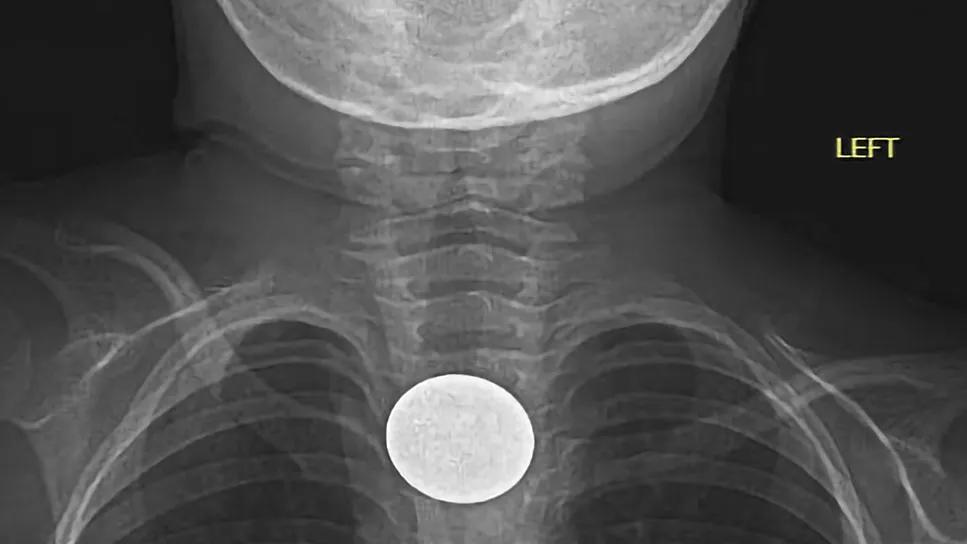

Anteroposterior X-ray showing swallowed coin

A few hours later, radiology contacted Dr. Appachi with a surprising finding: the X-ray revealed a coin was lodged in the child’s esophagus.

Lateral X-ray showing swallowed coin. Image at top of article: Anteroposterior X-ray view of the coin.

The patient ended up being treated by gastroenterology, who removed the coin — a quarter — via esophagogastroduodenoscopy. The team reported ulceration at the site of the coin, and found furrow-like outpouching in the esophagus, indicating that it had likely been there for several months.